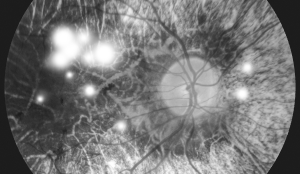

Diabetic Retinopathy

당뇨망막증이란?

당뇨가 발생하고 10년 이상이 되면 40%가 넘는 환자분들이 당뇨망막병증이 나타날 수 있는 당뇨 합병증으로

고혈당으로 인해 모세혈관에 손상이 생겨 망막의 말초 혈관에 순환장애가 발생하는 질환을 말합니다.

• 비증식성 당뇨망막증

비증식성 당뇨망막증

당뇨망막병증 환자의 약 80% 비율을 차지하며 망막혈관에서 피가 새어 나와 망막에 피가 고이고 붓게 되어 출혈이나 망막부종 등이 나타날 수 있으며, 방치할 경우 증식성 당뇨망막병증으로 진행될 수 있습니다.

• 증식성 당뇨망막증

증식성 당뇨망막증

시신경 표면에 비정상적인 신생혈관이 증식하는 단계로 쉽게 출혈을 일으키고 주위로 흉터들이 자라나와 망막을 잡아 당겨서 망막박리가 생기기도 하며 심할 경우 실명에 이르게 됩니다.

당뇨망막증 진단방법

당뇨망막증 초기에는 시력 저하 등의 자각 증상이 없으므로 당뇨병 진단시 망막이상이 없더라도 반드시 정기적으로 안과 검진을 받아야 합니다.

• 안저 촬영

• 형광안저혈관조영

• 빛간섭단층촬영